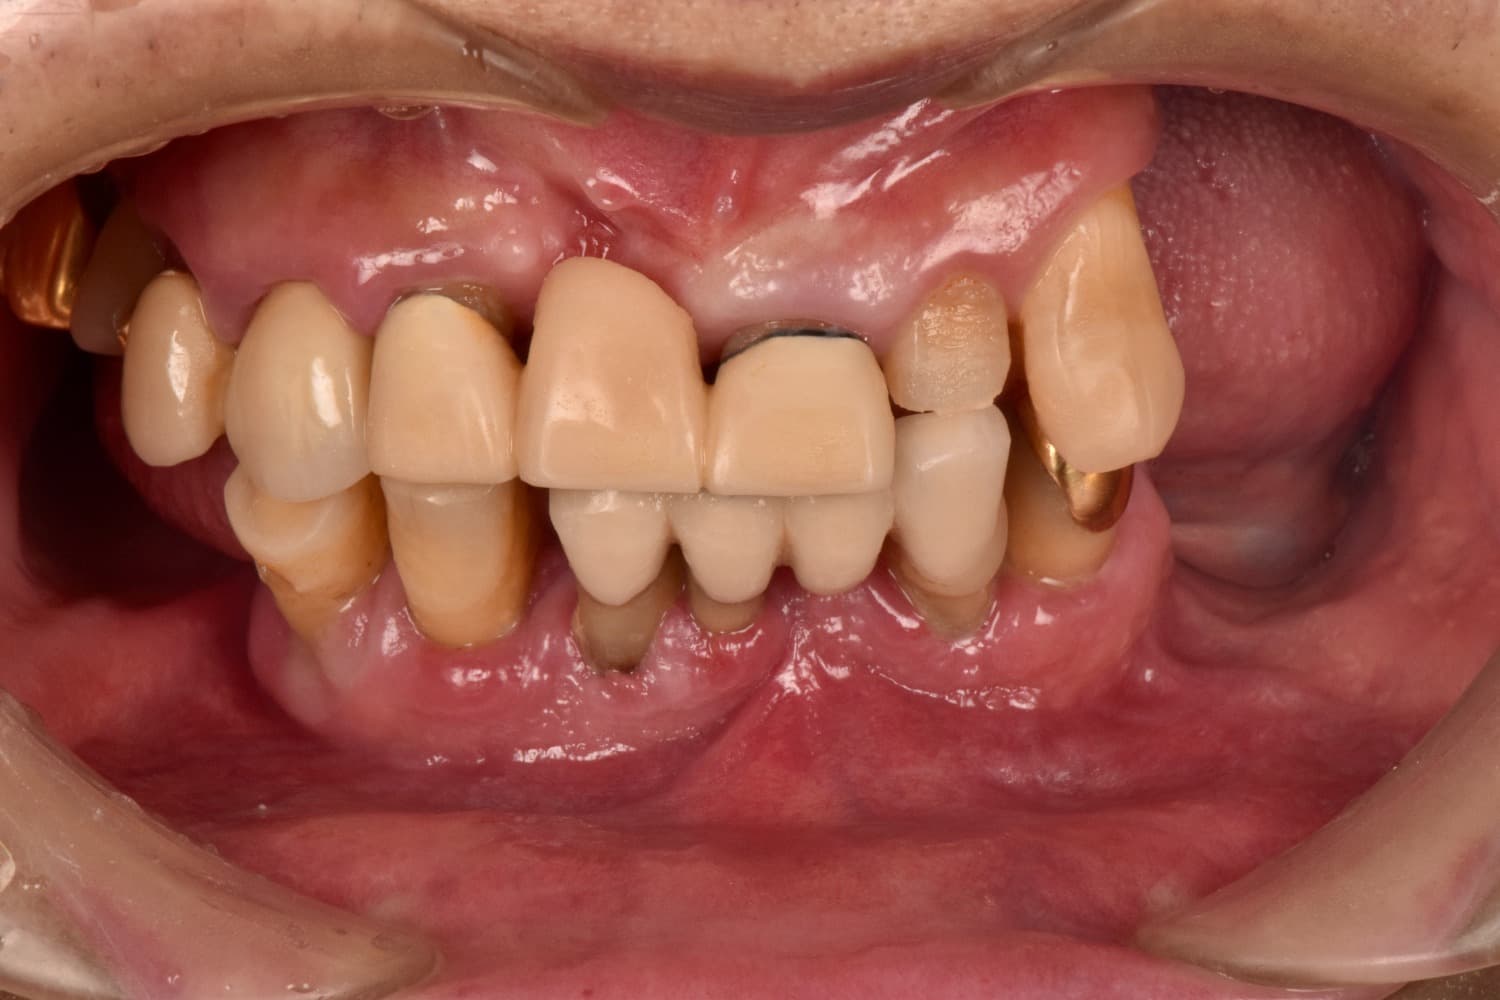

Before

重度の歯周病で上下すべての歯を抜歯せざるを得なくなった患者さまに対して、上下顎オールオン4で治療を行った。

年齢

70代

性別

男性

主訴

入れ歯が合わない 噛みにくい

治療期間

6カ月

治療回数

15回

費用

7,432,000円

副作用・リスク

清掃状態等により将来炎症を起こす可能性があります。